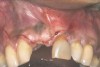

Fig 20. Papillae-sparing incisions were developed both horizontally and vertically. The pedicle flap was elevated, exposing a thin ridge.

Figure 20